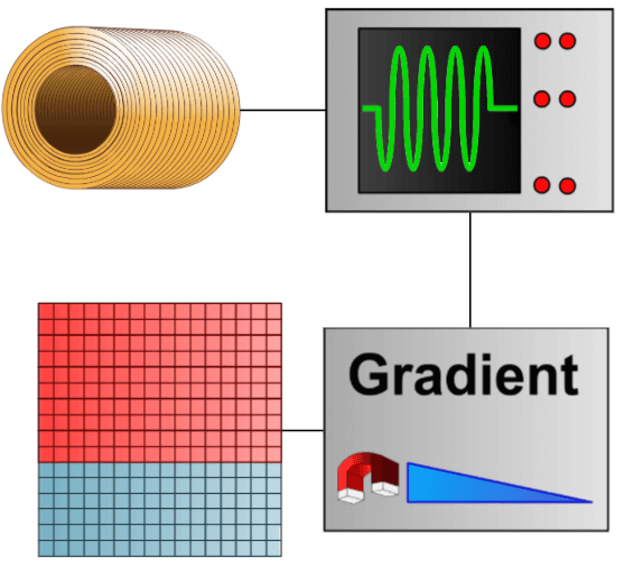

An RF wave is emitted, a signal is sensed and thanks to the use of the gradients, this signal is used to fill the mathematic space called Fourier space or K space. Once the K space is filled, we apply a mathematic formula that is a Double Fourier Transformation to obtain an image. The Fourier space is the frequential representation of the image.

The general principle of MRI can be summarized with a magnet, a radio frequency wave, a signal that is sensed, which is localized and treated through the use of gradients. This signal is used to fill a mathematical space called the Fourier space. We then get an image using a mathematical formula. These mathematical formulas are called algorithms.

Matrix or Battleship

The signal is arranged in the matrix like the ships in a game of battleship. The system sorts information according to their phase and frequency. Just like the game of battleship where the ocean is a grid of letters and numbers, the MRI Fourier space is a grid of phase and frequency.

The Frequency Matrix

While reading the signal, a magnetic field gradient is applied. Thus, the received signal is composed of several signals, each having a particular frequency. The frequency matrix corresponds to the number of different frequencies that make up the signal. In fact the size of this matrix influences the reconstruction time. The higher the number of frequencies in a signal, the longer it will take for the system to view it.